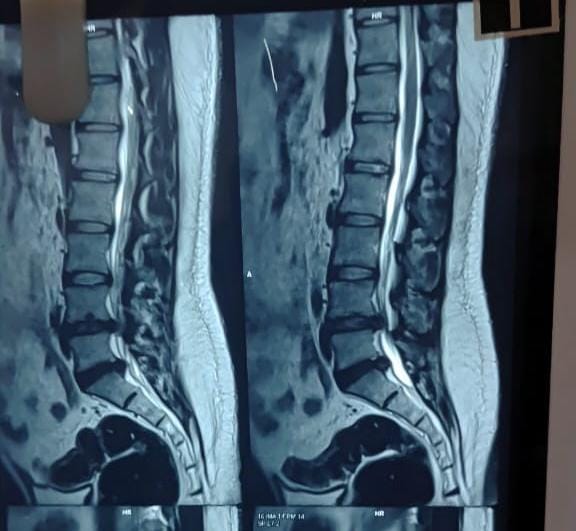

Sunshine Ortho Pain Superspeciality Hospital is the Best Multispeciality Hospital, Orthopedic Hospital in Wakad, Hnjewadi, PCMC and Pune. We are specialized in Orthopedic Surgeries, Robotic Joint Replacement Surgery, Hip and Knee Replacement Surgery, Complex Trauma And Pelvi Acetabular Surgery, Spine Surgery, Sports Medicine And Arthroscopy, Regenerative Therapy/Prolotherapy, Shoulder Surgery, Knee Surgeries, Foot And Ankle Treatment in Wakad, Hinjewadi, PCMC and Pune.